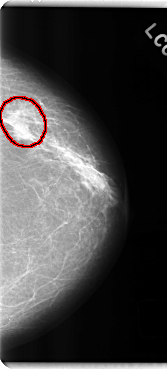

C_0185_1.LEFT_MLO

LEFT_MLO LINES 4768 PIXELS_PER_LINE 2504 BITS_PER_PIXEL 12 RESOLUTION 50 OVERLAY

FILE: C_0185_1.LEFT_MLO.OVERLAY

TOTAL_ABNORMALITIES 1

ABNORMALITY 1

LESION_TYPE MASS SHAPE LOBULATED MARGINS ILL_DEFINED

ASSESSMENT 5

SUBTLETY 5

PATHOLOGY MALIGNANT

TOTAL_OUTLINES 1

BOUNDARY